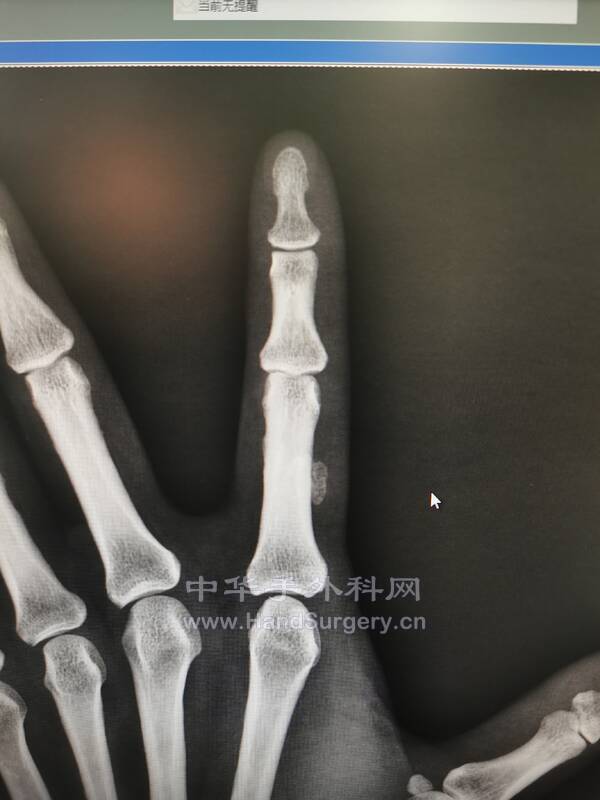

src=http___img.dxycdn.com_upload_2014_11_08_43_12286145.snap.jpg&refer=http___im.jpg

丁香园上的图片,像什么

病房有一个类似的病人

今天手术一个类似的病历

IMG_20210909_093659.jpg

IMG_20210909_093716.jpg

IMG_20210909_093842.jpg